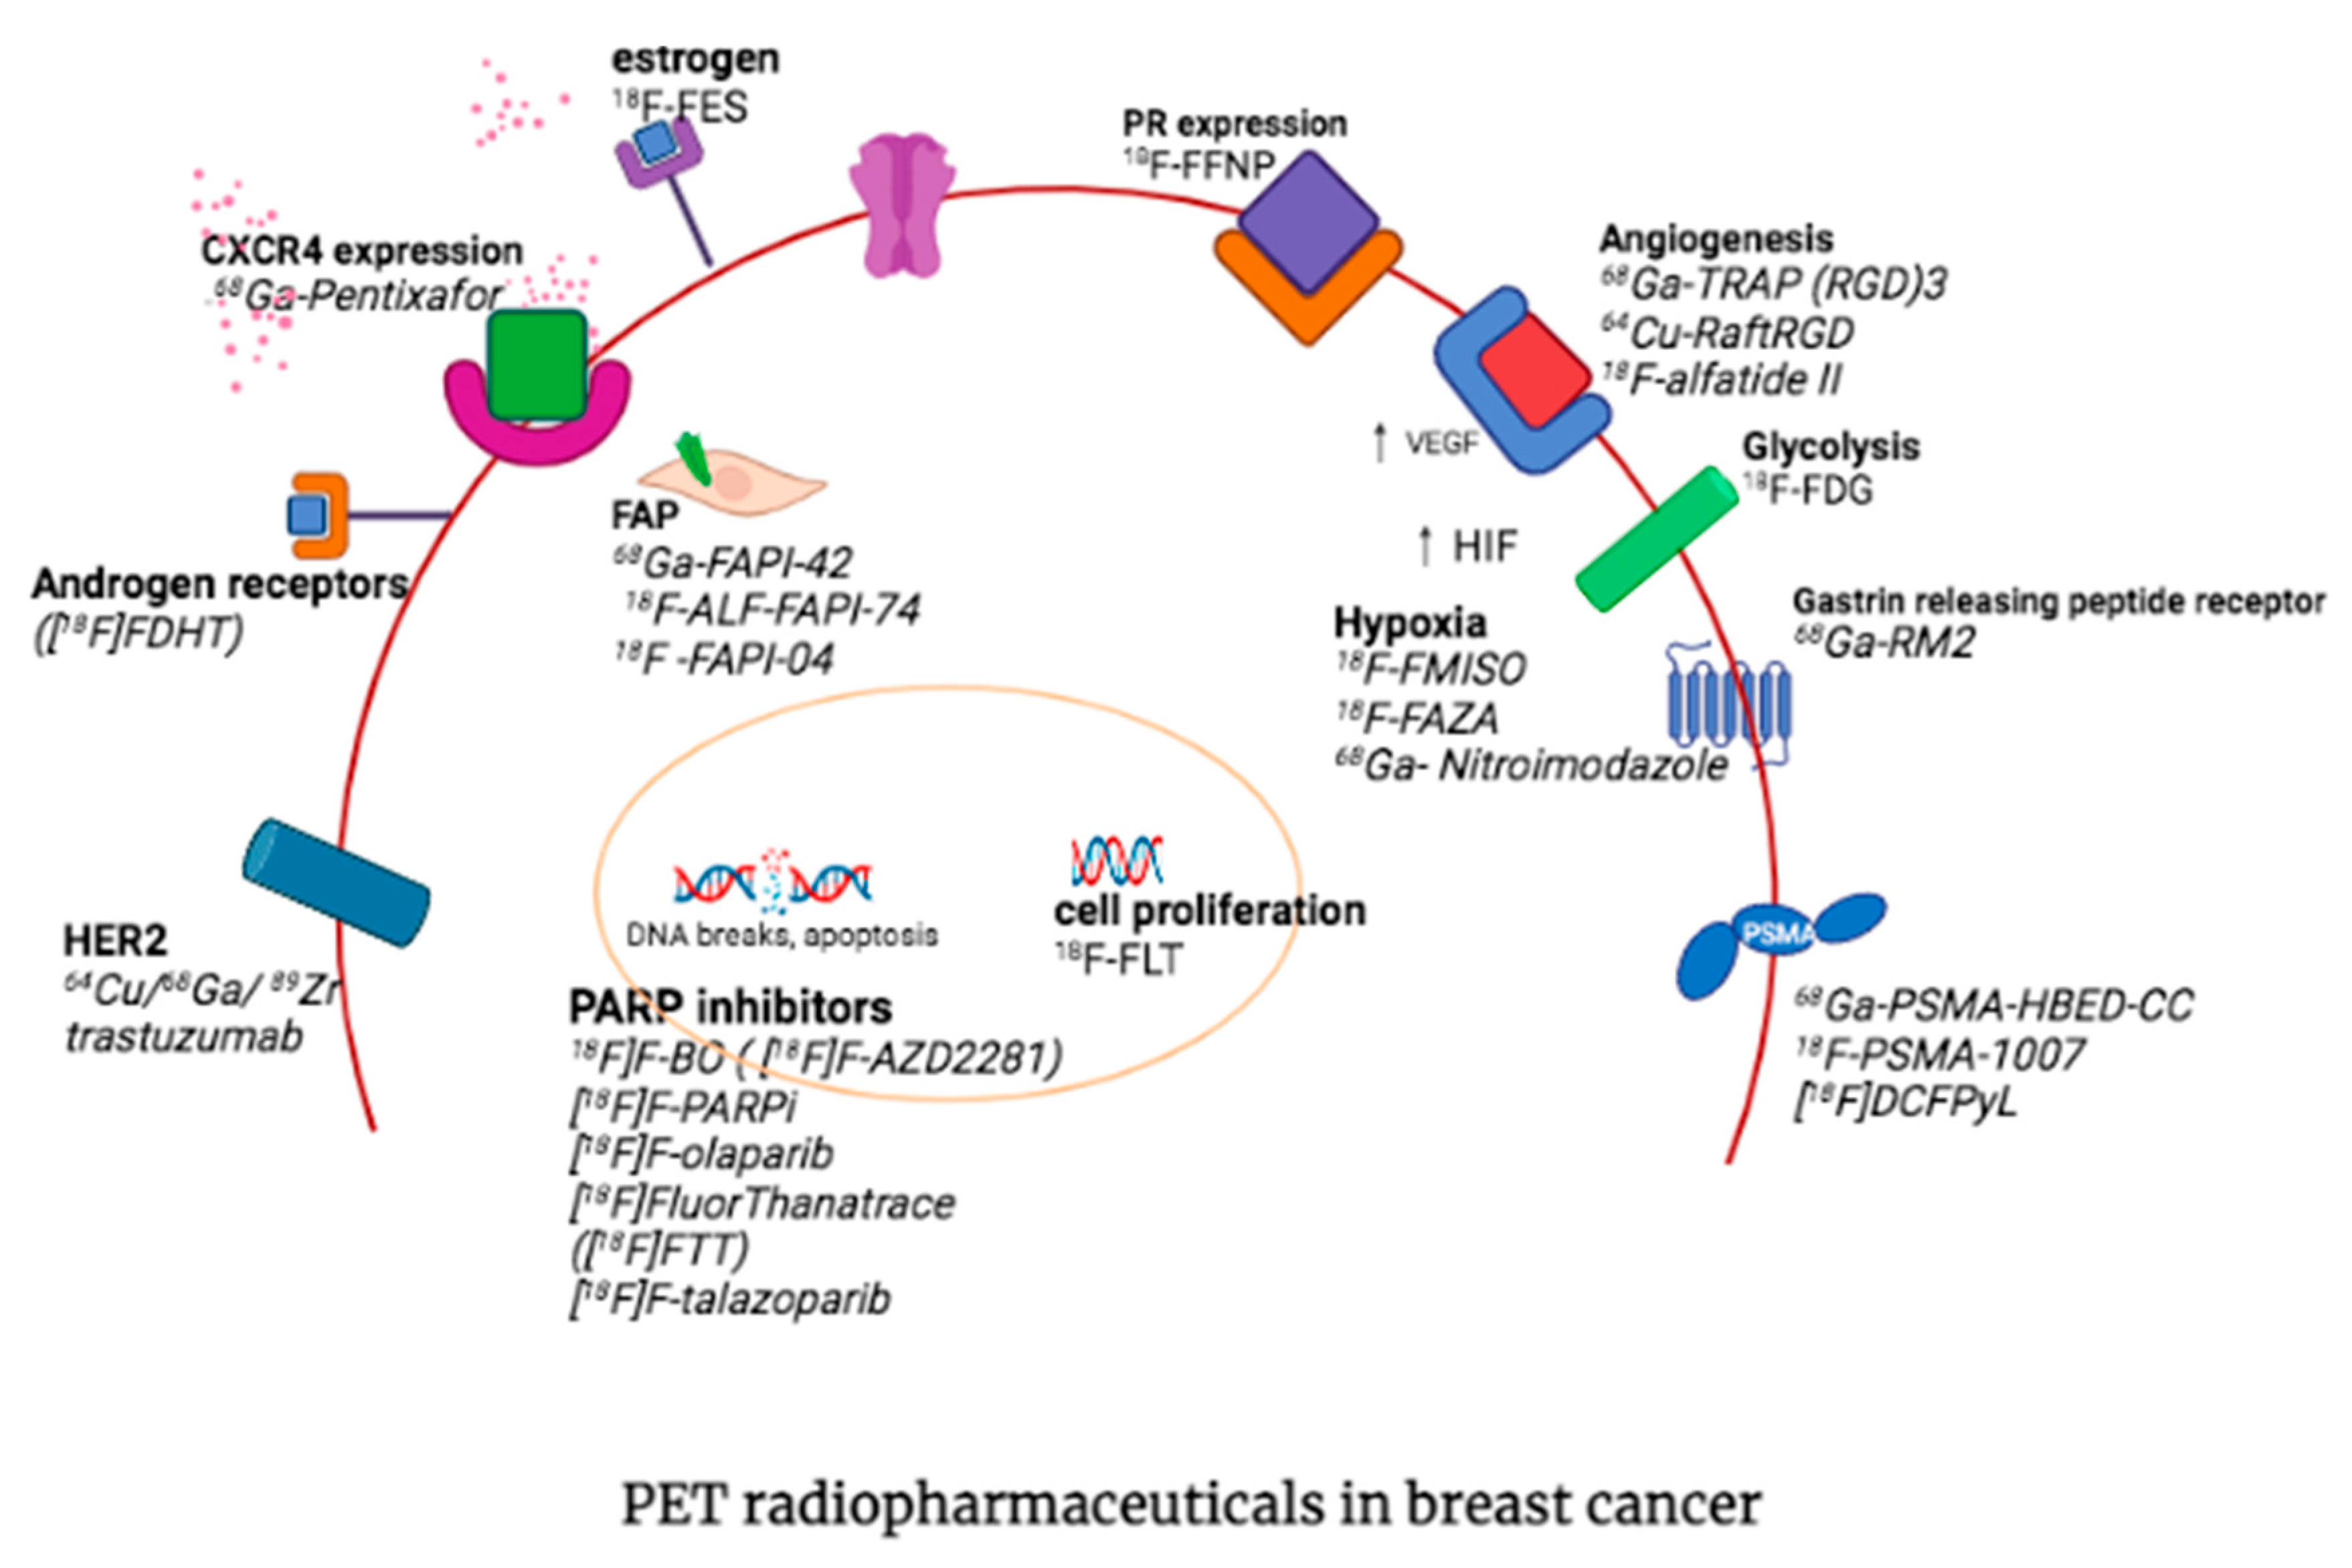

3. Other PET Radiopharmaceuticals in Molecular Imaging of Breast Cancer

3.1. Fibroblast Activation Protein

3.2. Prostate-Specific Membrane Antigen

3.3. Chemokine Receptor 4

3.4. Estrogen Receptor Imaging

3.5. Progesterone Receptor Imaging

3.6. Human Epidermal Growth Factor Receptor 2 (HER2)

3.7. Androgen Receptor

3.8. Somatostatin Receptor Expression

3.9. Integrins

3.10. Gastrin Releasing Peptide Receptor

3.11. PARP Inhibitors

3.12. Hypoxia Imaging